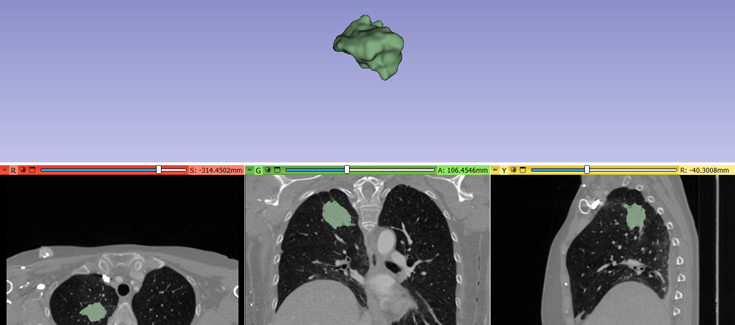

Gracias a un nuevo estudio publicado en Journal of Translational Medicine, se ha identificado un biomarcador no invasivo para predecir el beneficio clínico duradero de la inmunoterapia, basado en la integración de datos radiómicos y clínicos monitorizados, durante los primeros meses de tratamiento con anticuerpos monoclonales anti-PD-1/PD-L1, en pacientes con cáncer de pulmón no microcítico avanzado.

La identificación de biomarcadores predictivos no invasivos de la respuesta a la inmunoterapia es crucial para evitar interrupciones prematuras del tratamiento o prolongaciones ineficaces. Un biomarcador se utiliza a veces para determinar la respuesta del cuerpo a un tratamiento para una enfermedad o afección.

La inmunoterapia se ha convertido en uno de los tratamientos de referencia del cáncer de pulmón avanzado no microcítico, con tasas de respuesta prometedoras, enfermedad que sigue presentándose con una frecuencia alta. La predicción de la eficacia de la respuesta al tratamiento antes y durante el tratamiento, sigue siendo crítica para el manejo personalizado de los pacientes.